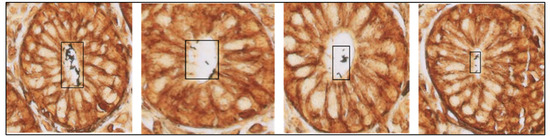

3.1. The Algorithm Can Automatically Detect H. Pylori on Gastric Samples